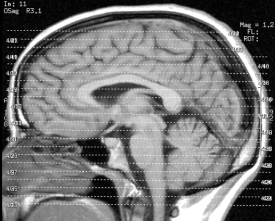

Hirn: Scan der Aktivität verrät Inhalt von Gedanken. Bild: FlickrCC/Liz Henry